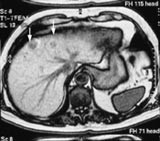

De positive leverspesifikke kontrastmidlene kan inndeles i ekstracellulære kontrastmidler, som består av en rekke gadoliniumkelater, og intracellulære kontrastmidler, som tas opp spesifikt i hepatocyttene. I denne gruppen finnes Mangafodipir trisodium (MnDPDP), som er tilgjengelig på det norske markedet (2). De negative leverspesifikke kontrastmidlene er intracellulære kontrastmidler som tas opp i kupfercellene (det retikuloendoteliale system) (3). De leverspesifikke kontrastmidlene skal være til hjelp for å oppdage flere lesjoner i lever (fig 1). Enkelte publikasjoner oppgir at de også kan brukes til å skille mellom forskjellige typer lesjoner (2, 3). I Norge er det få tilfeller av primær hepatocellulær cancer, det blir derfor mest aktuelt å lete etter metastaser, og å skille metastaser fra benigne lesjoner, hyppigst hemangiomer og cyster. Det blir, i daglig bruk, en problemstilling tilsvarende den vi har for ultralyd og CT, bare med høyere sensitivitet for å finne lesjoner og en høyere spesifisitet når det gjelder å skille malignt fra benignt (3).